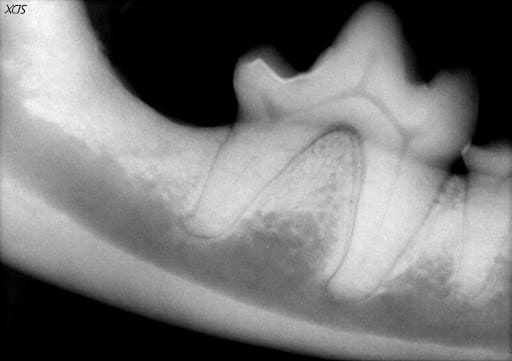

Moderate attachment loss of the tissues around a tooth requires more aggressive tactics. Open root planing with guided tissue regeneration is a procedure that serves this purpose. In guided tissue regeneration, a gingival flap is created to expose the root surface for cleaning and debridement due to the depth of the attachment loss. Once the infected tissue is removed and the root surface meticulously cleaned, different types of bone graft material are placed in the deep pocket and the gingival flap is surgically closed. This procedure allows for osseous (bone) regeneration around the root structure and regrowth of the periodontal ligament. This procedure also carries an excellent long term prognosis when performed by a board-certified veterinary dentist.

Figure 5. A large mandibular molar in a dog with severe bone loss from periodontal disease. Unfortunately, the small molar to the left could not be saved and was surgically extracted.

Figure 6. The same tooth 6 months after an open root planing and guided tissue regeneration procedure. The lost bone and periodontal ligament have been regenerated.